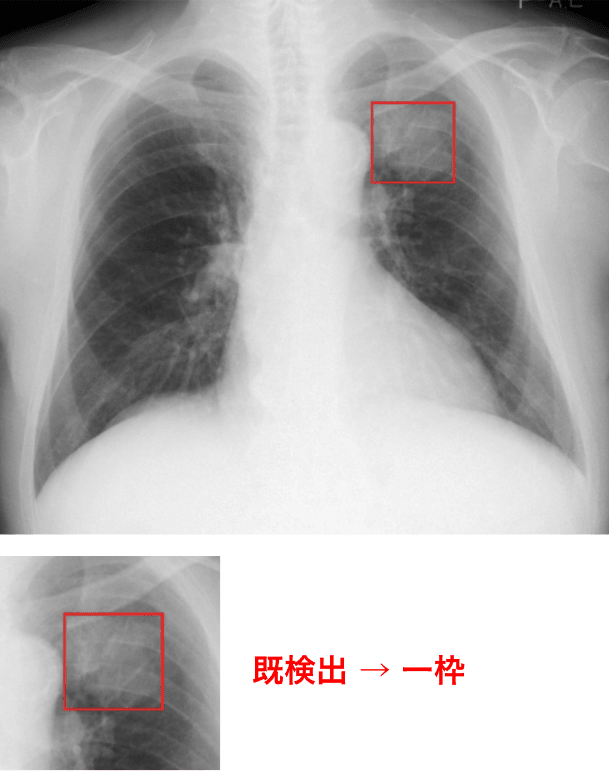

過去画像との比較をサポート

過去に解析された同一患者の胸部X線画像と現在の画像を自動で比較し、異常陰影候補領域の経時的変化を表示します**。

過去比較

過去に撮影された同一被験者の胸部X線画像を比較し、異常陰影候補領域の経時的変化を強調表示します。

<例>

* Noduleモードの場合。XRモードの場合は、新規検出のみ